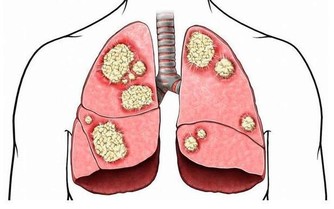

如果長期受寒,寒氣收斂易導致肌肉緊張,經絡不通暢,影響全身氣血運行

而薑是邪寒的“宿敵”,這時及時喝點薑茶,有助於驅逐體內風寒。